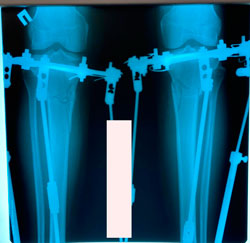

на фиксации

image-31-10-20-02-18.jpg

image-31-10-20-02-18-4.jpg